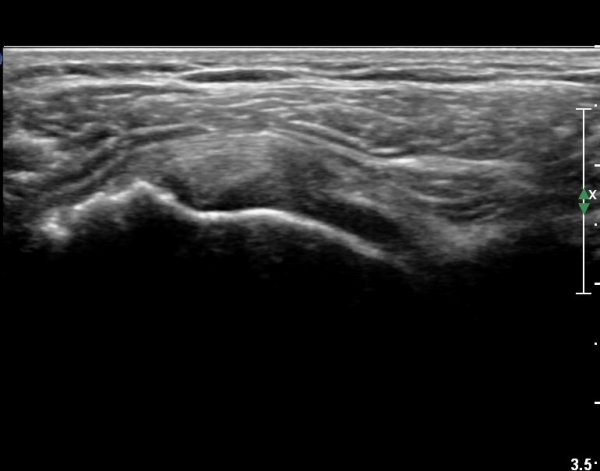

ŽÃËÀÚ¸¦ Á¶±Ý ¾Æ·¡·Î À̵¿ÇÏ¿© À̵ιڱٰÇÀÇ È¾´Ü¸é°Ë»ç¿¡¼­ ÀÌµÎ¹Ú±Ù°Ç ÁÖÀ§ ¼ö¾×Àú·ù°¡ °üÂûµÈ´Ù(»çÁø 3, 4).

À̴ Ȱ¾×¸·¿°Áõ ¼Ò°ßÀ¸·Î Ãæµ¹ÁõÈıº ¶Ç´Â ȸÀü±Ù°³ ÆÄ¿­ ½Ã ÈçÈ÷ °üÂûµÇ´Â

¼Ò°ßÀÌ´Ù.